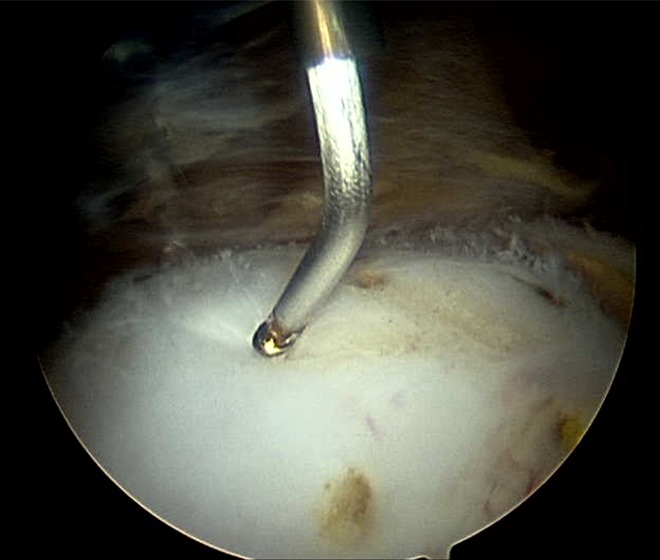

The operative procedure was performed according to our routine practice. Antibiotics and thromboprophylaxis were given. Patients were in the lateral decubitus position using the McCarthy hip distractor, although no traction was applied. Ultimately, 2 peritrochanteric portals were used to access the lateral compartment, and AGB/ITBR was performed. First, the iliotibial band was cut in a cruciate pattern from its superficial surface and the corners then removed to leave a diamond-shaped defect in the iliotibial band overlying the greater trochanter. The trochanteric bursa was then excised using a combination of radiofrequency ablation and an arthroscopic shaver. Patients allocated to AGB/ITBR + RFMD subsequently underwent RFMD using a Topaz device (ArthroCare) (Figure 1). An average of 8 to 10 punctures were made into the gluteus medius and minimus tendons with the probe in a grid-like pattern at differing depths (see Video Supplement). Each RF “pulse” was controlled for a 0.5-s duration and generated a temperature of 40°C to 70°C. At the completion of surgery, all patients received a 20-mL injection of bupivacaine at 0.5%, adrenaline 0.020 mg, morphine 5 mg, and ketorolac 30 mg into the pre-existing bursal space. Portal closure with a single absorbable monofilament suture was performed in all patients.

Figure 1.

Arthroscopic radiofrequency microdebridement (RFMD) of the superior surface of the gluteal tendons of the hip.